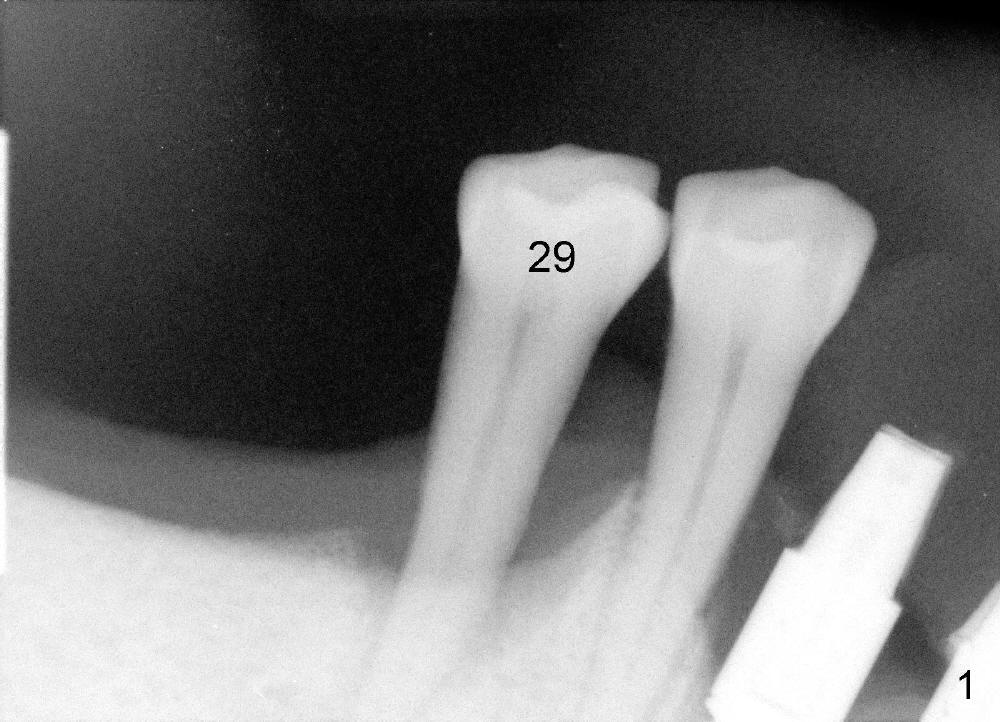

To avoid paresthesia on the right side, several preop PAs are taken (Fig.1-4) so that we know how to take good X-ray for this gagging patient.  At first, #2 Sensor is used to take the first PA (Fig.1).  It does not show the apex of the tooth #29.  The second PA is a little better (Fig.2), but the mental nerve is out of view.  Then #1 sensor is used.  It allows us to position the sensor lower (Fig.3), but the image is blurred.  When it is retaken, the image is clear (Fig.4), showing the proximity of the mental nerve loop (Fig.4': red dashed line) to the root tip of the tooth #29 (R).